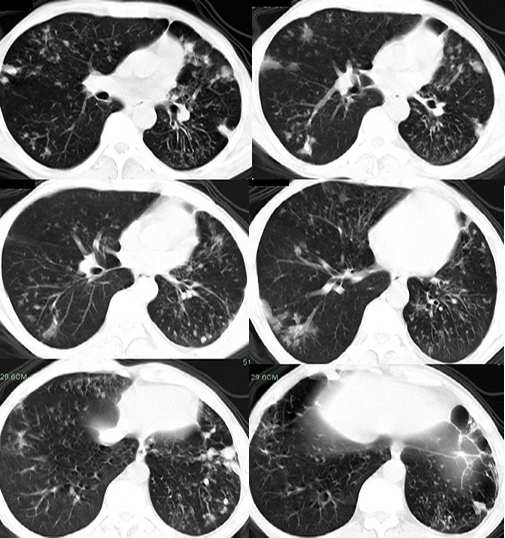

男,58岁,胸痛、咳嗽一周,无痰血;否认其他特殊病史

两肺结核(空洞,支气管播散灶)并左肺纤维化,支扩,肺大炮,胸膜肥厚粘连。

两侧胸廓不对称,左侧明显变小,两肺上叶可见空洞,纤维条索影,两肺下叶多发斑片状影。考虑两肺上叶继发性肺结核伴两肺下叶支气管播散。

影像;两上肺及左中下肺多个大小不一薄壁不规则空洞,部分空洞可见少量液平,周围拌有条索影,纵隔,心脏左移,两中下肺多发散在小结节以及小囊状阴影。

考虑;慢纤洞伴两肺下叶支气管播散。肺结核合并症---支扩。

两侧胸廓不对称,左侧明显变小,两肺上叶可见空洞,纤维条索影,两中下肺多发散在小结节、斑片状以及小囊状阴影。考虑两肺上叶继发性肺结核伴两肺下叶支气管播散及感染。